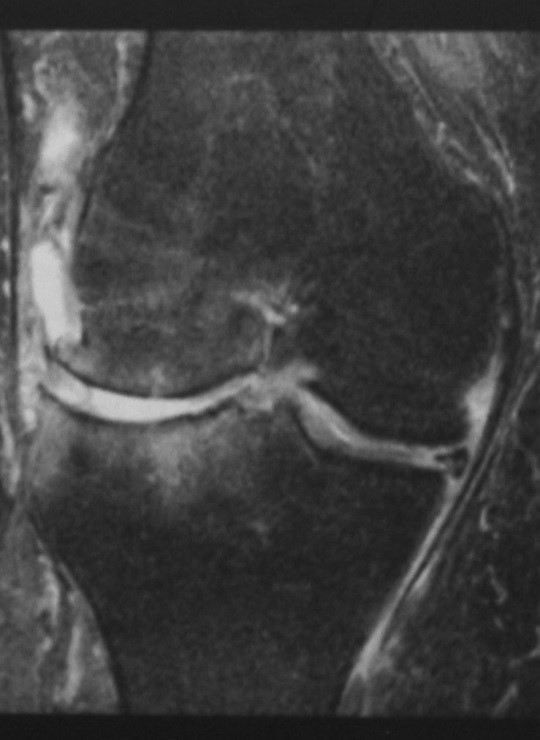

Остеоартрит коленного сустава МРТ (корональная проекция, последовательность STIR) демонстрирует исчезновение хрящевой ткани в латеральных отделах, выпот в полости сустава, дегенерацию мениска и субхондральный отек кости, предположительно как реакция на нарушение биомеханики.

Рис. 1. Рентгенограмма и МРТ коленных суставов больной З.,62 лет. На рентгенограмме (А) выраженное сужение медиальных отделов суставной щели, краевые остеофиты, субхондральный склероз. На МРТ(Б) краевые приострения, выраженные дегегнеративные изменения в медиальных отделов субхондральной кости, выраженное истончение медиального отдела хряща. Дегенерация медиального мениска

Вследствие нарушения равновесия между образованием нового строительного материала для восстановления хряща и его разрушением, хрящ истончается, на нем появляются язвы, обычно только в наиболее нагружаемой части сустава [5]. МРТ в сравнении рентгенографией более чувствительна в выявлении истончения хряща в латеральном отделе коленного сустава. На МРТ обнаруживалось истончение суставного хряща в латеральных отделах сустава, которые на рентгенограмме не проявлялись изменением суставной щели. Так как большая часть нагрузки приходится в медиальные отделы коленного сустава, изменения суставного хряща начинается с этой части сустава. На рентгенограммах в первую очередь суживается медиальные отделы суставной щели. При этом латеральные отделы суставной щели остаются не измененными и даже несколько расширяются. Это приводит к ложному выводу о интактности суставного хряща в этом отделе, изменения которого достоверно выявляется на МРТ (см.рис.3). Этим можно объяснить более низкую встречаемость изменения суставного хряща в латеральном отделе коленного сустава на рентгенограммах (23 суставах).

МРТ показывает истончение хряща в этом же отделе